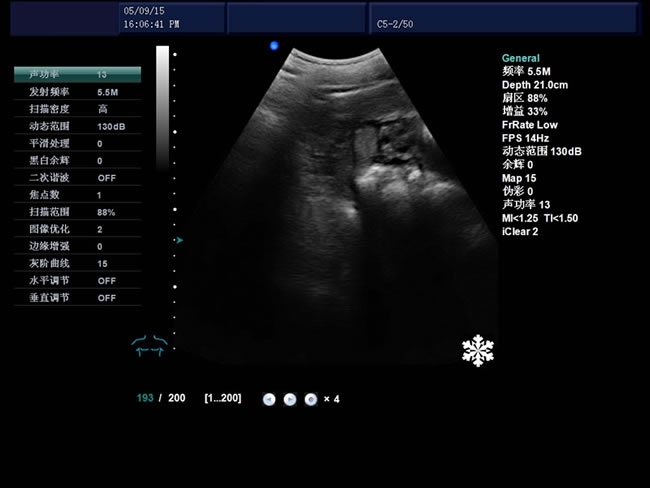

S9 彩色多普勒獸用超聲診斷儀

• S9彩色多普勒獸用超聲診斷儀是徐州市大為電子設備有限公司推出的一款全新的彩色超聲診斷儀器。

電影回放存儲